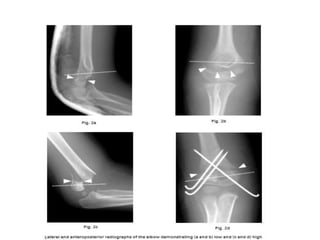

• To determine the level of fracture, a reference line was

defined on the sagittal radiograph at the isthmus of the

distal humerus, and on the AP radiograph as a line con-

necting the medial epicondyle, the olecranon fossa and

the lateral epicondyle.

 High fractures - defined as those exclusively

above the reference line.

low fractures - below or involving the reference

line.